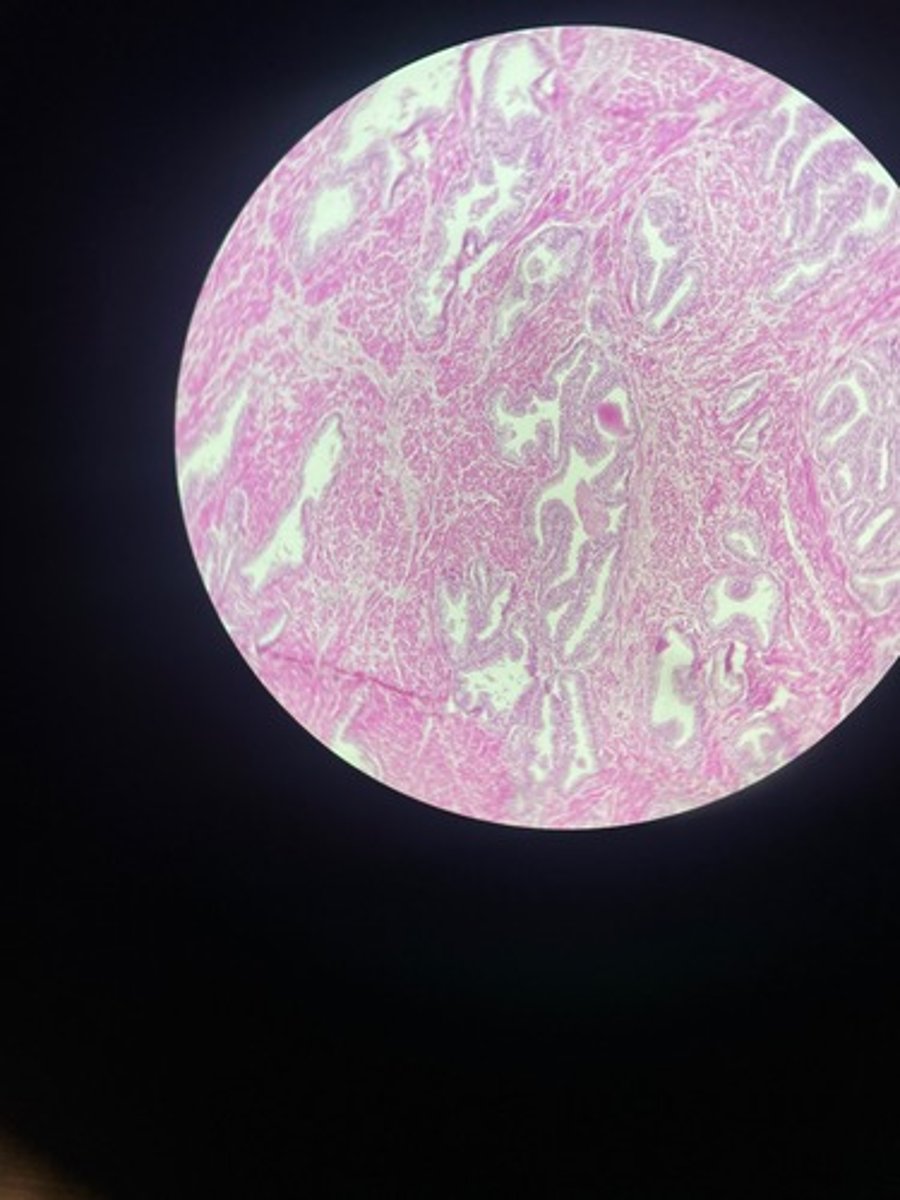

Ureter HE

Ureter HE

Ureter HE

Ureter HE

Ureter HE